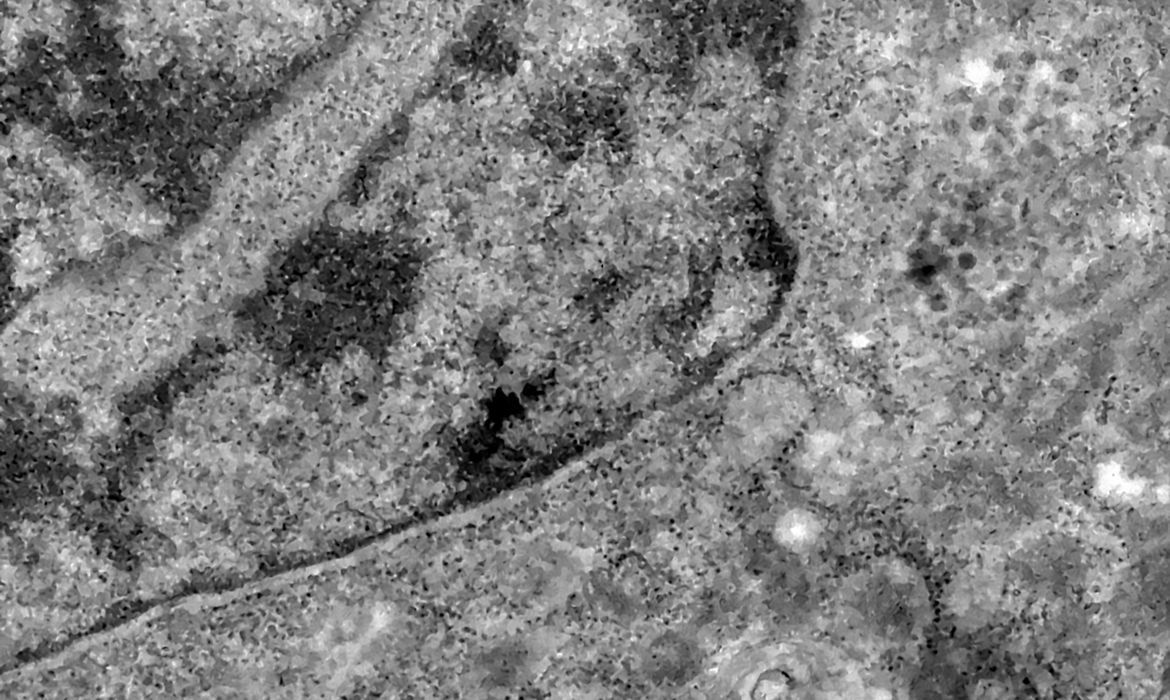

Covid-19: pesquisa associa casos graves a desgaste do sistema imune

Estudo publicado por pesquisadores do Instituto Oswaldo Cruz (IOC/Fiocruz) e da Universidade Federal do Rio de Janeiro (UFRJ) apontou que casos graves de covid-19 estão relacionados a um processo de envelhecimento do sistema imunológico que ocorre durante a doença. A pesquisa está disponível na revista científica Journal of Infectious Diseases e foi divulgada pela Agência [...]